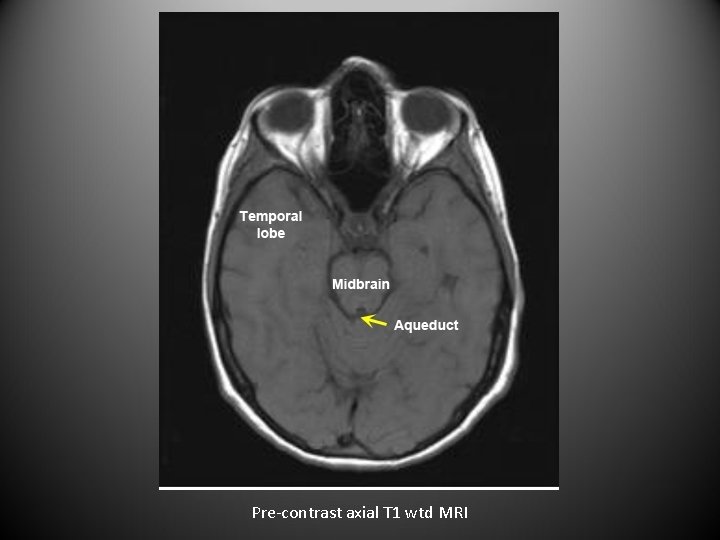

• For axial images you need to know the level. • The next set of images are axial sections of brain from top to bottom.

Pre-contrast axial T 1 wtd MRI